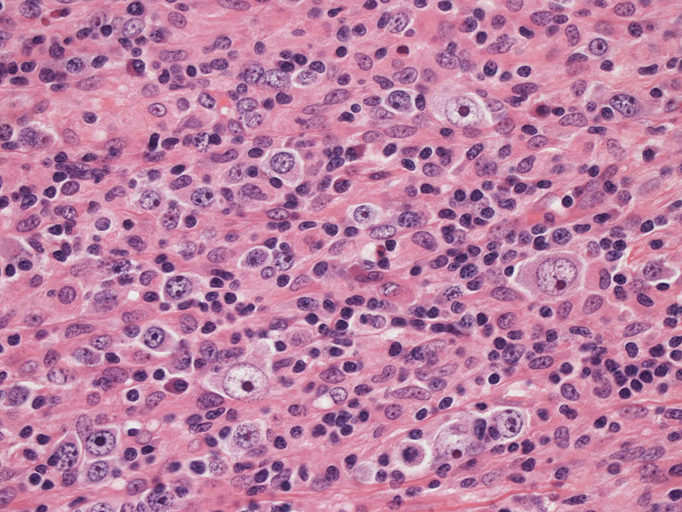

結節構造内では, 好酸性細胞質をもつ組織球の増生を背景に大型異型細胞が散在性または集蔟して増殖している。被膜下にも線維化組織内にbizzarreな大型細胞が認められる。リンパ球は小型リンパ球が大型異型細胞を含む組織球性の結節辺縁に存在する。大型細胞は, centroblastic cellが多く, その他 Hodgkin cell-like cell, RS細胞様巨細胞, 腎臓型の核をもった細胞, 多型核の細胞など多彩な形態を示す。異型核分裂像をふくむ核分裂像が多い。

大型異型細胞の形態

| Hodgkin cell-like | centroblastic | centroblastic | multinucleic |

| anaplastic large | kidney-shaped | mirror image | atypical mitosis |